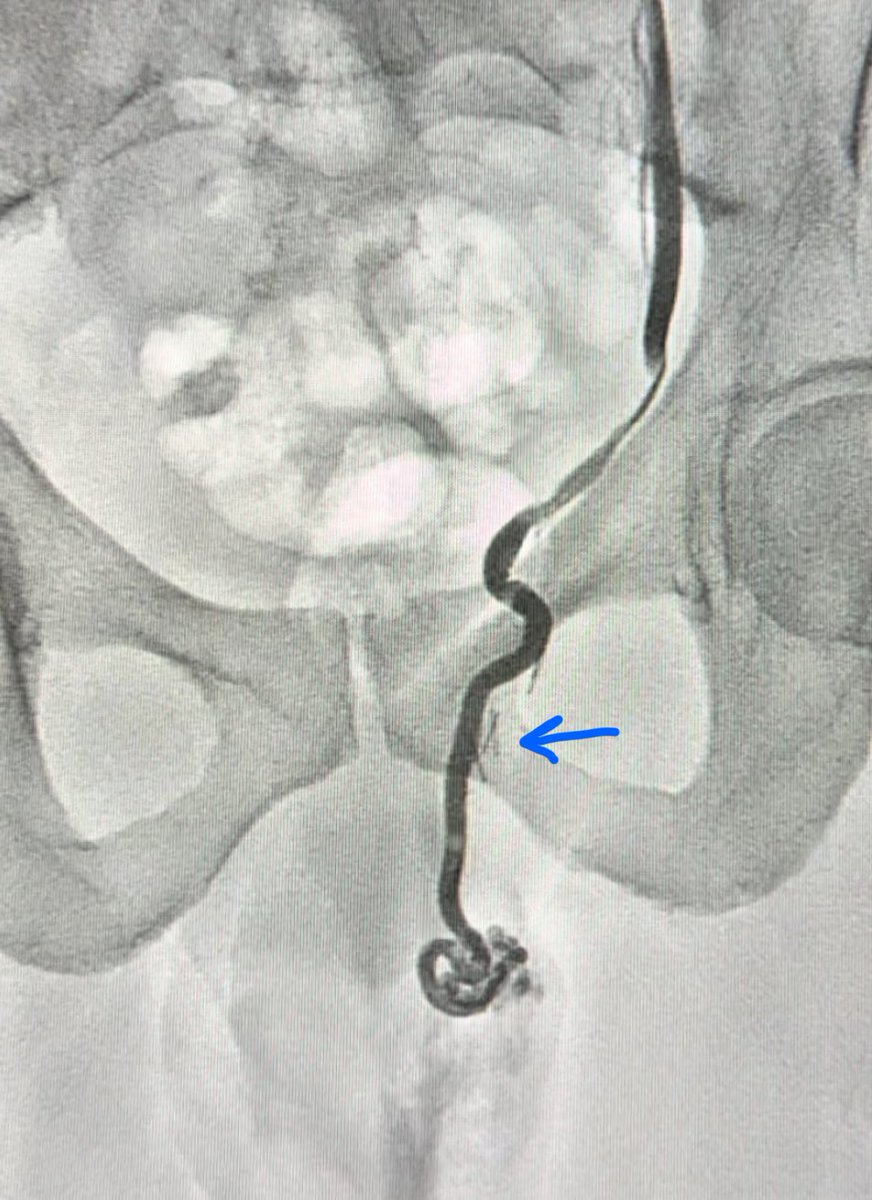

١٥- هذه الطريقة فشلت بسبب أن الربط يتم بمكان واحد ومن المعلوم ان الوريد الخصوي يغذيه اوردة كثيرة جداً وربطه في مكان واحد غير فعّال ابداً. أوردة كثيرة تتصل بالوريد الخصوي ، منها اوردة جوانب الظهر ، غلاف الكلية ، ووريد القولون (السهم الملون) كما بالصورة المرسوم وبصورة واقعية من اجراء القسطرة والعلاج بالصمغ الطبي. لا تجد احداً من جراحين المسالك يتكلم عن هذه التفاصيل حتى بالدراسات بسبب انها لا تتوضح جراحياً اساساً.

٢٣- هل القسطرة تعمل بطريقة واحدة؟ كما قلنا مسبقاً يتم اغلاق الوريد الخصوي باللفائف المعدنية او الصمغ الطبي. الاختيار يكون غالباً بناءً على خبرة الطبيب ، توفر الادوات ، التكلفة ، و كذلك حجم ومواقع الأوردة الخصوية. هذه الدراسة وضحت أن الصمغ الطبي هو أفضل خيار بأقل نسبة عودة للدوالي (بسبب تغلغله بالأوردة). كذلك الصمغ الطبي يختفي مع الوقت ولا يبقى له أثر بالأشعة (بخلاف الخيوط الجراحية واللفائف). ماهي عيوبه؟ تكلفته أعلى في بعض المراكز الطبية ويحتاج الى خبرة. بالأسفل صورة لمريض قد سبق وعملت له جراحة فتق إربي(موضح كلبسات تثبيت الشبكة) ، تم تحويله للقسطرة (لاحظ كيف يتغلغل الصمغ الطبي بالأوردة) بحكم أن الجراحة السابقة تزيد من نسبة حصول المضاعفات خاصة موت الخصية.